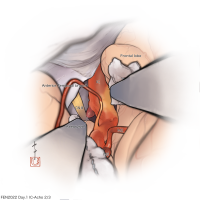

FEN2022シリーズ